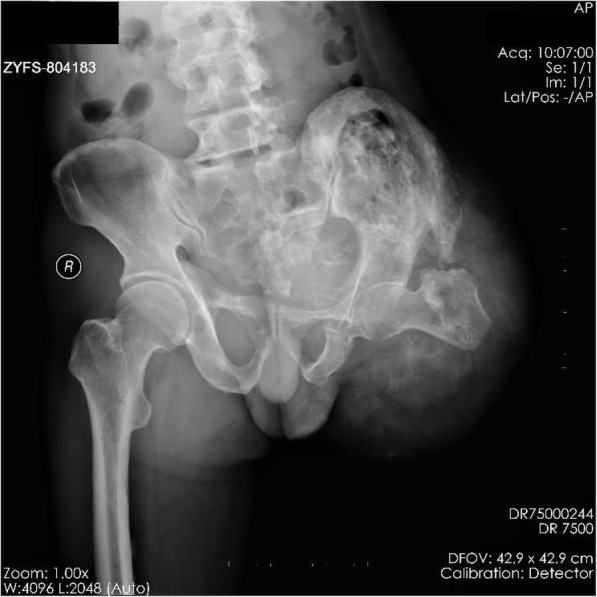

The patient claimed to have a “port-wine birthmark” on the left foot at birth. With growth and development, the port-wine stain started to spread, and the entire left lower limb was progressively flexed and contracted with loss of function. The condition stabilized after his growth stopped. Magnetic resonance imaging (MRI) suggested diffuse soft tissue hemangiomas, and a diagnosis of KTS was made based on the medical history and clinical characteristics (Fig. 2a and b). A technetium 99 m-methyl diphosphonate (99mTc-MDP) bone scan also indicated extensive radioactivity concentration on the flexor side of the limb, and a diagnosis of HO was inferred (Fig. 2c). However, it was difficult to distinguish whether the high-density shadow and radioactive concentration exhibited on imaging was intramuscular calcification or ossification.

Fig. 2.

Additional imaging studies. a-b Magnetic Resonance Imaging (MRI) shows extensive high signal foci within the muscles; c Technetium 99 m-methyl diphosphonate (99mTc-MDP) bone scan shows radioactivity concentration at the flexor side of the limb